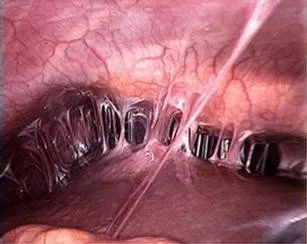

- Laparoscopy (gold standard): "Violin-string" adhesions between the liver capsule and peritoneum.

- Inflammation of liver capsule → "violin-string" adhesions.

- Fitz-Hugh-Curtis syndrome (perihepatitis) causes RUQ pain from "violin-string" adhesions on the liver capsule.